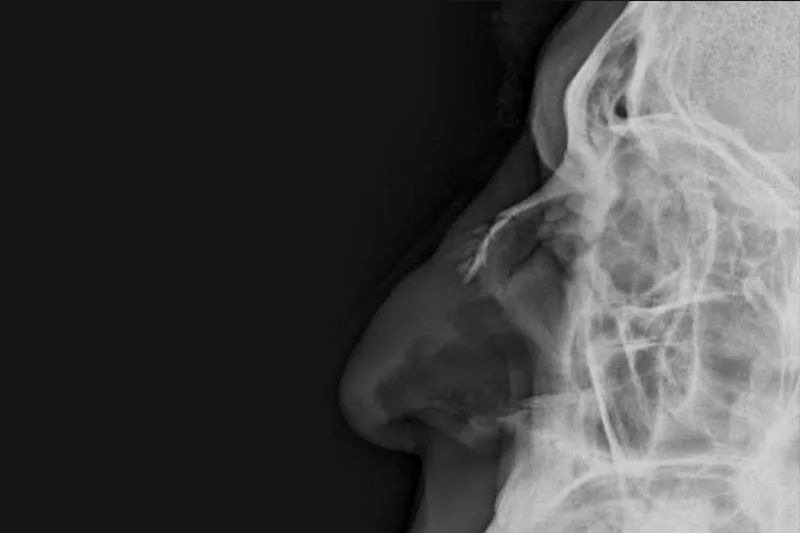

A nasal fracture, is a fracture of one of the bones of the nose commonly caused by assault, trauma during sports, falls, and motor vehicle collisions. Symptoms may include bleeding, swelling, bruising, and an inability to breathe through the nose. They may be complicated by other facial fractures or a septal hematoma. Diagnosis is based on the signs and symptoms and confirmed by plain X-ray or CT scan PNS. Minor nasal fractures may be allowed to heal on their own provided there is not significant cosmetic deformity.